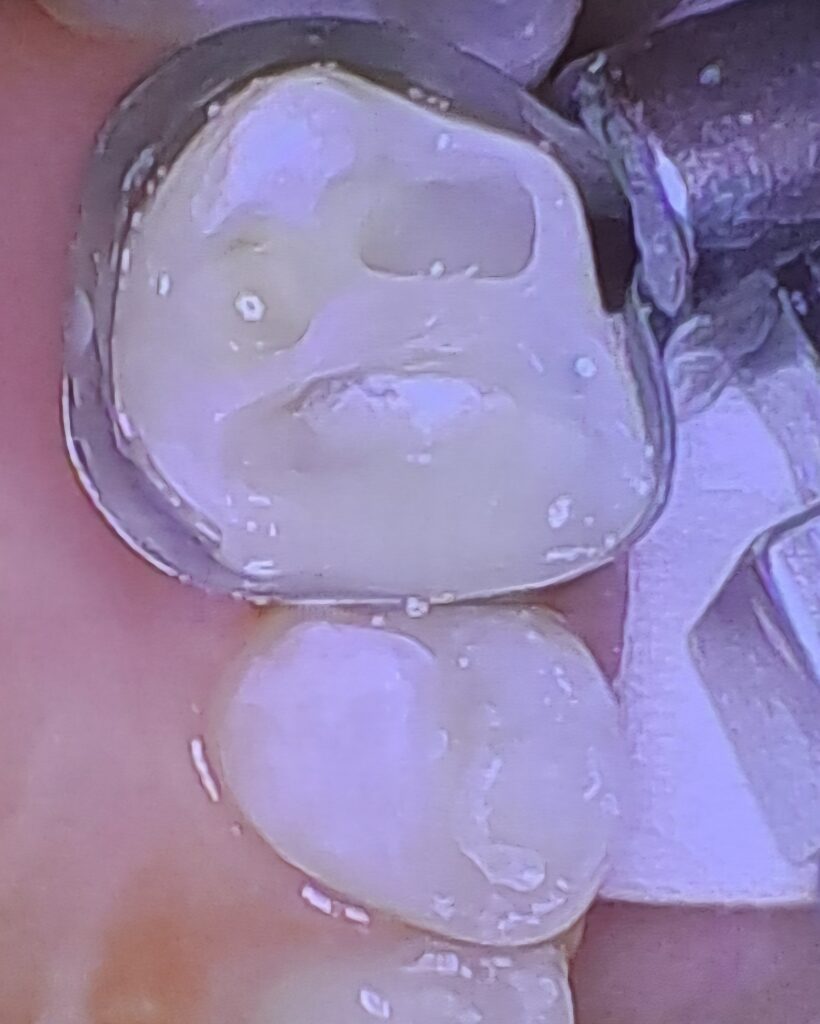

عکس های قبل و بعد جرم گیری و عصب کشی دندان پزشکی رایان

عکس های قبل و بعد جرم گیری و عصب کشی دندان پزشکی رایان

نمونه کارهای قبل و بعد از تحویل روکش دندان پزشکی رایان

قبل از تحویل یک واحد روکش

بعد از تحویل روکش